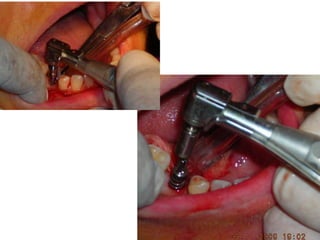

Dogmar Dasgupta,March,2009

Immediately after operation

On 11th.March,2009.

Favorable implant-bone interface:Attributed by……. •Strictly following the basic fundamental surgical protocol for one-stage one-piece implant •Bone drilling at a very very low speed •Use of surgical tap in D1 & D2 type of bone •Immediate temporaries: out of occlusion